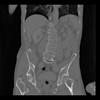

35 CUERPO,CE,Coronal,3.000,CUERPO,Coronal,